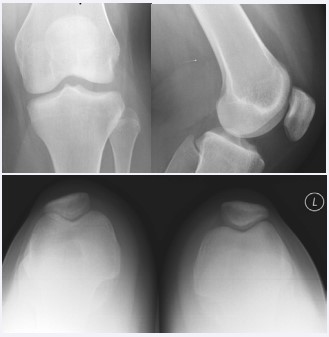

Physical exam of the left knee revealed abnormal 4+ lateral compartment translation with a poor endpoint as opposed to 3+ on the right, with a fixed end point. Anterior drawer, Lachman, and coronal plane stability testing were normal bilaterally. Anteroposterior, lateral and sunrise radiographs of the left knee revealed no abnormalities (Figure 2). MRI of the same knee revealed a Wiberg type II/III patella with normal trochlear depth, TT/TG distance (Figure 3), trochlear inclination, and no trochlear dysplasia or intercondylar notch narrowing. The ACL, PCL and both menisci were normal.

Figure 2: Anteroposterior, lateral and sunrise radiographs of the left knee revealed no abnormalities.

Figure 3: Sagital image from MRI.